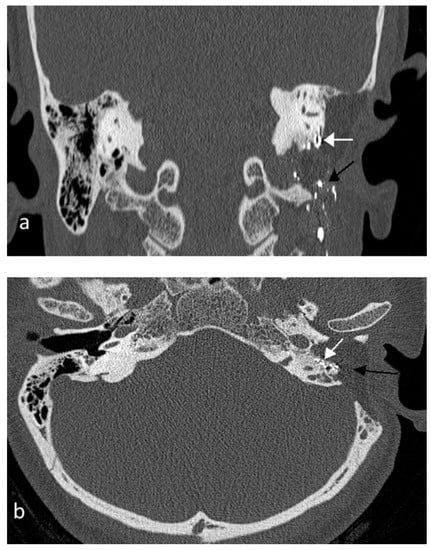

2. Case Presentation